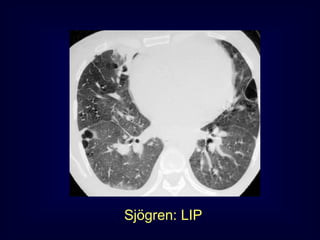

LIP = Lymphocytic Interstitial

Sjögren: LIP

Pneumonia

Rarely idiopathic

In association with:

Sjögren‟s syndrome

Immune deficiency syndromes, AIDS

Primary biliary cirrhosis

Multicentric Castlemean‟s disease

LIP = LymphocyticInterstitial Pneumonia Benign lymphoproliferative disorder Diffuse interstitial infiltration of mononuclear cells Not limited to the air ways as in follicular Bronchiolitis

LIP = LymphocyticInterstitial Pneumonia Rarely idiopathic In association with: Sjögren‟s syndrome Immune deficiency syndromes, AIDS Primary biliary cirrhosis Multicentric Castlemean‟s disease

Sjoegren disease Dry eyeand dry mouth Fibrosis, bronchitis and bronchiolitis LIP Up to 40 x increased risk for lymphoma (mediastinal adenopathy) and 2 x times increased risk for neoplasma Overlap Sarcoid, DM/PM, MXCT SLE, RA (pleural effusion)